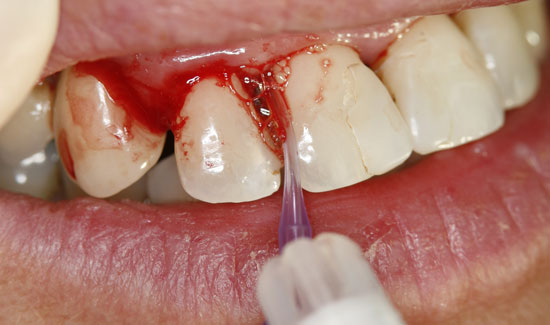

Fig. 2: Clinical aspect of region 12, formation of gas bubbles on the inflamed tissue. Continuous suction in the vicinity of the area of use